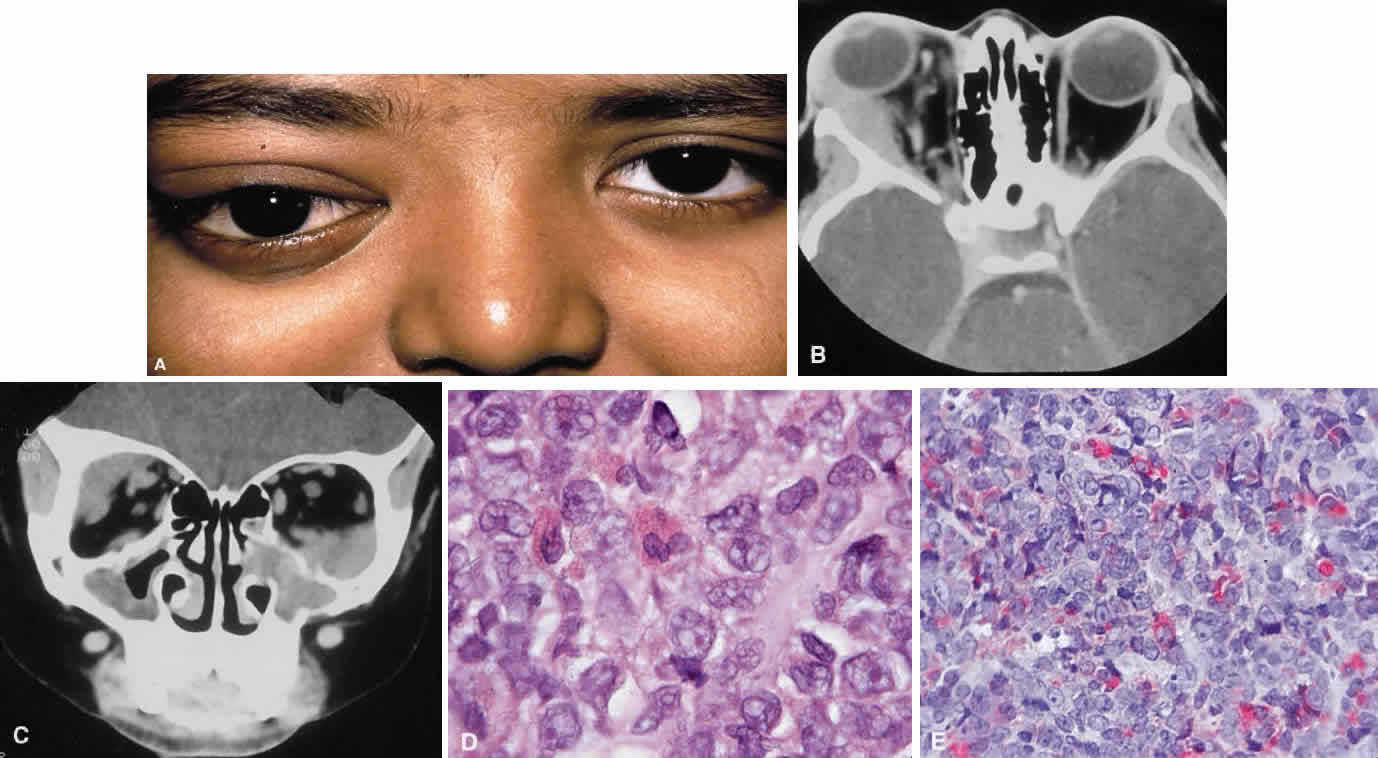

Systemic non-Hodgkin's lymphomas usually present with painless lymph node enlargement in one or more nodes. Adults usually are in their fifth or sixth decade, and presentation in childhood is extremely rare. The fever, night sweats, and weight loss characteristic of Hodgkin's disease generally are absent. Splenomegaly may develop in 20% of patients. Patients usually have normal blood counts, although they may develop lymphocytosis, especially with well-differentiated lymphocytic lymphomas, or pancytopenia with anemia, hemorrhage, petechiae, ecchymosis, and infection—the pancytopenia occurring in one third of patients as a result of bone marrow involvement or chemotherapy and radiation. Patients with B-cell lymphomas tend to develop difficulty with bacterial infection, whereas those with T-cell lymphoma may develop difficulty with delayed-type hypersensitivity and viral infections. Leukemic conversion is rare in adults, although it occurs in 25% of children. In children, an acute leukemic phase may be the initial presentation. Furthermore, children are more likely to develop extranodal and aggressive disease, although they may respond well to therapy.50 In a series of 1269 patients, of whom only 3 (0.42%) presented initially with proptosis, one third of patients presented with extranodal disease and a few with bone marrow invasion.51 There was a 1.3% incidence rate of orbital disease secondary to systemic lymphoma.